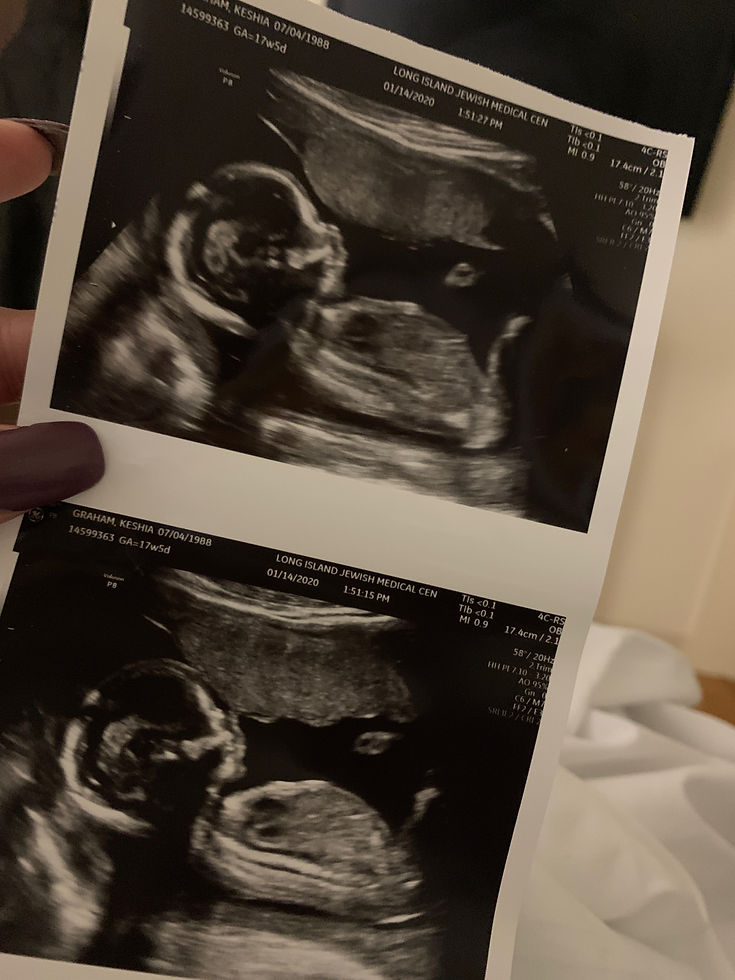

Today is my first full day at home with my daughter since she was born. Writing that still feels unreal. She’s here, sleeping beside me, and I’m sitting in pain, exhausted, emotional, and trying to understand how this is my life now.

I’m overwhelmed in ways I didn’t fully prepare for. I’m a first-time mom, a single parent, running on little sleep, and my body is still recovering from surgery. At the same time, I’m genuinely happy and thankful. I had a safe pregnancy. I had a C-section. My daughter is healthy. I know how much worse this could have gone, and that gratitude lives right alongside everything else I’m feeling.

What makes this moment heavier is how fast everything happened. On June 4th, I went in for what was supposed to be a regular doctor’s appointment. I didn’t know that appointment would turn into an emergency C-section and a three-day hospital stay. I was having contractions, but my body couldn’t feel them. My baby could. She felt everything. Her heart rate was low, and suddenly the room felt serious in a way I couldn’t ignore.

I had placenta previa and was suffering from pre-eclampsia, made worse by my history of hypertension. My anxiety and depression were already present, and in that moment, everything collided. I found myself questioning if I was doing the right thing, questioning if I was ready, questioning if I could really do this. I was stressed, overwhelmed, and trying to process information faster than my mind could keep up. Then I was rushed into an inpatient stay. At that point, there was no more weighing options or second-guessing. This baby was coming—whether I felt ready or not.

She was born on June 5th.